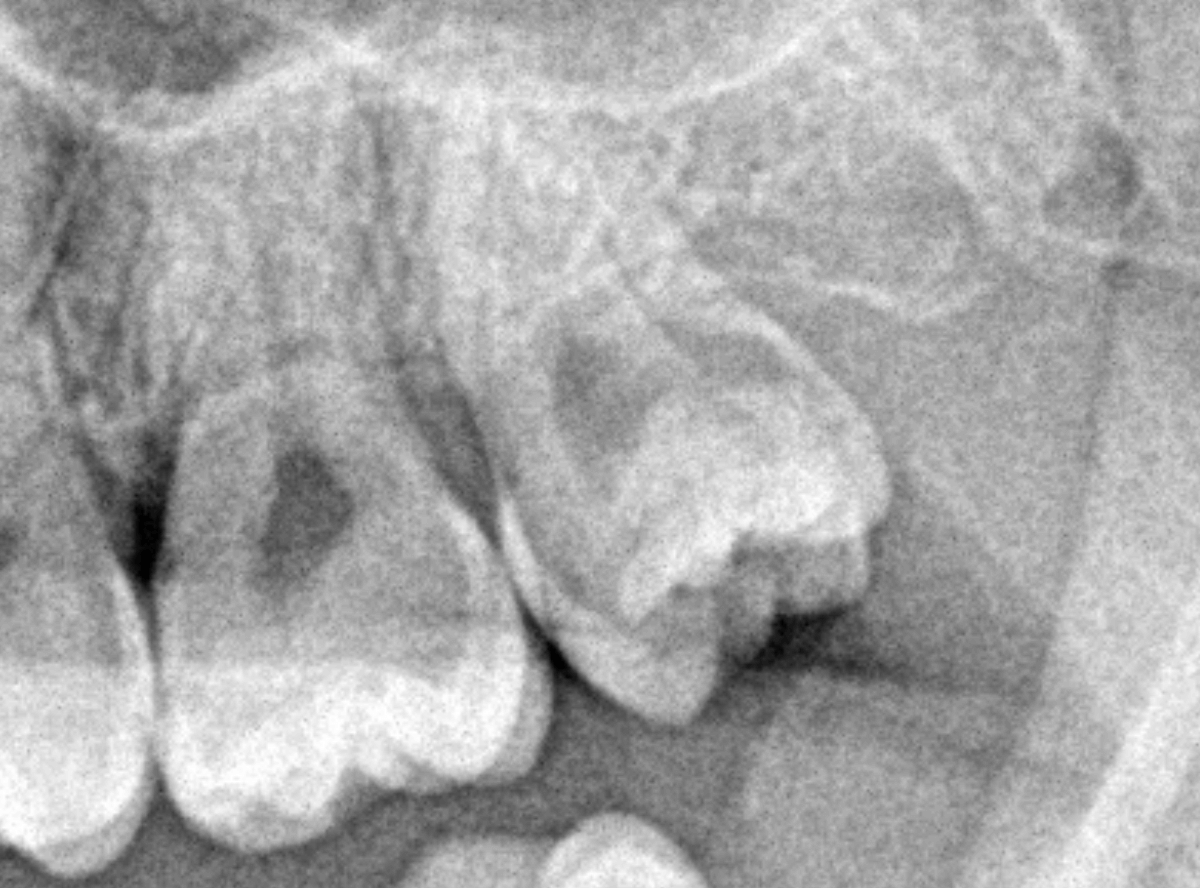

ここでは、比較的簡単なおやしらずの抜歯の例を中心にご紹介します。

このようなおやしらず、あなたはありませんか?